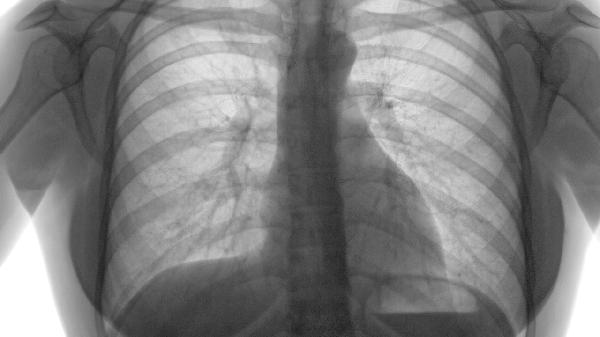

当肺气肿合并肺结核、流感病毒或肺炎链球菌感染时,痰液中可能携带相应病原体。结核杆菌可通过飞沫核传播,需进行痰涂片抗酸染色检测确认。急性感染期痰液变黄绿色或带血丝时需警惕传染可能。

限局性肺气肿是肺组织局部过度充气膨胀的病理状态,可能由慢性支气管炎、支气管阻塞、肺部感染、遗传因素等原因引起。 ...